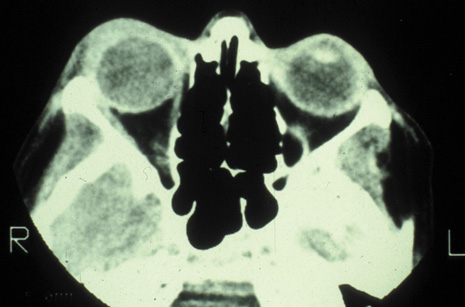

Magnetic resonance imaging (MRI) is purported to be more useful than CT in the diagnosis of preseptal cellulitis. It is less reliable at diagnosing the subtle signs of muscle enlargement and periscleritis and thus is not as useful in differentiating orbital cellulitis from other inflammatory orbital diseases.71 On MRI with gadolinium contrast, orbital cellulitis may show a smearing or linear streaking of the normal fat shadows on T2-weighted images. MRI is excellent for demonstrating localized fluid collections such as abscesses. It is not helpful in distinguishing a transudate from an exudate, because both appear liquid and are of low intensity on T1-weighted images and bright on T2-weighted images (Fig. 19).

Fig. 19. Magnetic resonance image of preseptal cellulitis with anterior abscess formation.